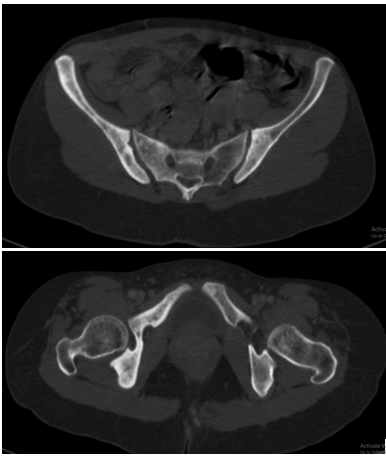

Bệnh nhân đi khám tại bệnh viện Bạch Mai được chụp cắt lớp vi tính lồng ngực phát hiện các đám tổn thương đông đặc phổi 2 bên, tổn thương đặc xương không đều các đốt sống D5, D8, D11 và xương sườn IV bên phải.

Hình 2, 3: Hình ảnh đặc xương không đều các đốt sống D5, D8, D11 và xương sườn IV bên phải.

Hình 6, 7: Hình ảnh đặc xương không đều cánh chậu 2 bên.